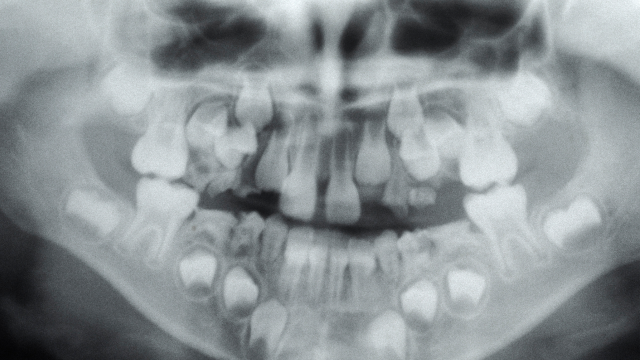

아이의 치아 배열과 턱 성장을 함께 고려하는 성장기 교정

턱뼈의 성장 방향과 속도를 고려해, 치아 발달을 유도하는 교정으로,

우리 아이의 치아는 아직 완성되지 않았습니다.

혼합치열기 교정

유치의 탈락과 영구치의 맹출이 진행될 때 시행하는 교정으로 치아 교체 시기와 맞물린 시기이기 때문에 의료진의 성장 예측과 경험이 중요한 교정입니다.